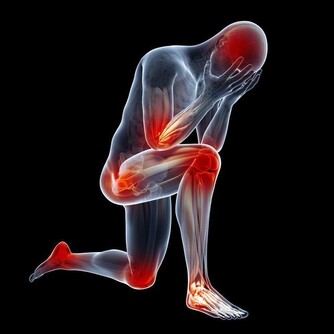

幹點活就腰酸腿疼。特別是中年女性,只要站的時間一長,就會覺得腰酸腿痛。咳嗽時,腿還會出現放射性疼痛。如果小腿肚出現壓痛更要注意,說明腸胃已經開始「罷工」了。

雙腿一側發涼。即使夏天也總感到小腿肚涼颼颼的,有時還覺得從臀部開始,到腳後跟,中間一條線都涼涼的。這可能是血液循環不暢造成的,也可能和腰椎間盤病變有關。

腫脹。血液循環不好會導致腿脹,同時這也是心腦血管病或腎臟疾病患者常有的症狀。

髖膝關節疼痛。幾乎所有關節都會隨著年紀增大而變得脆弱,特別是髖、膝這兩處關節。如果你發現在下樓梯、蹲下或跳躍時出現不適,甚至腿部有摩擦磨損、卡住動不了的感覺,說明關節已經急需保護了。